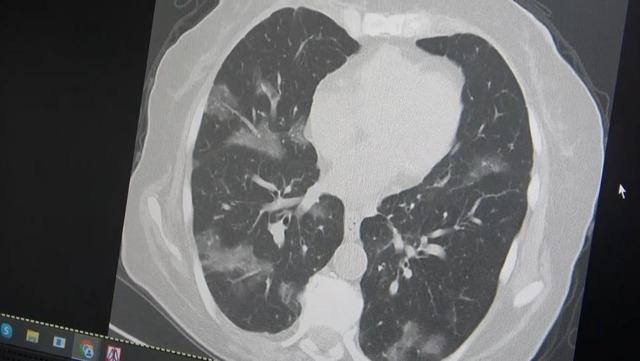

Kanserli bir hastanın akciğerlerinden örnek veren Özkaya, şöyle konuştu: “60 yaş üstü olması ve kemoterapi görmesi nedeniyle virüsün akciğerlere rahatlıkla indiğini görüyoruz. Bu yaza damgasını vuracak yeni virüsün bu olduğunu düşünüyoruz” dedi.

Öksürüğünüz geçmiyor. İsmine uygun olarak flört ediyormuş gibi süzülüyor. Son dönemde özellikle Kovid-19'un başlangıcında gördüğümüz vakalar gelmeye başladı. İlk başta güçlü akciğer tutulumu gördük. 2024 yılı başından bu yana neredeyse hiç akciğer tutulumu görmedik ama son günlerde vakalar gelmeye başladı. Kanser hastaları özellikle risk altındadır. Kemoterapi alan ve vücut direnci düşük olan kişilerde akciğer tutulumu görülür. Özellikle yurt dışı tatil ve hac ziyaretlerinden dönen kişilerin yaşlılarla ve vücut direnci zayıf olan kişilerle bir araya gelmelerini önermiyoruz” dedi.